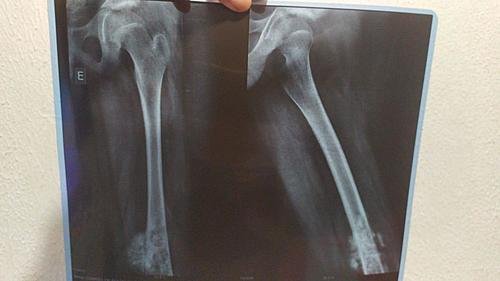

Gabriel De Souza Machado Tem 11 Anos E Devido A Dor E Inchaço Na Perna No Dia 29/01/2020 Fez Um Raio-X Que Detectou Um Tumor Na Perna Esquerda Com 17cm. Outros Exames Foram Feitos E Dia 03/02/2020 Infelizmente Foi Confirmado Um Câncer. Mais Exames Estão Sendo Feitos E Tomografia,Cintilografia, Biópsia. Porém Esses Exames Estão Sendo Feitos Em Minas Gerais Onde Será Dado Inicio Ao Tratamento. Nesse Momento Além Dos Gastos Com Os Primeiros Exames Estamos Tendo Muitos Gastos Com Transporte, Hospedagem E Alimentação. Agradecemos A Todos Que Puderem Ajudar, Não Só Com As Doações Mas Também Orações E Compartilhamento Para Alcançarmos Mais Pessoas

Gabriel De Souza Machado is 11 years old and due to pain and swelling in his leg on 29/01/2020 he underwent an X-ray that detected a 17cm left leg tumor. Other exams were done and on 03/02/2020 Unfortunately a cancer was confirmed. More Exams Are Being Taken And Tomography, Scintigraphy, Biopsy. However, these exams are being done in Minas Gerais where treatment will begin. At this moment, in addition to the expenses with the first exams, we are having many expenses with transportation, accommodation and food. We thank everyone who can help, not only with donations but also prayers and sharing to reach more people